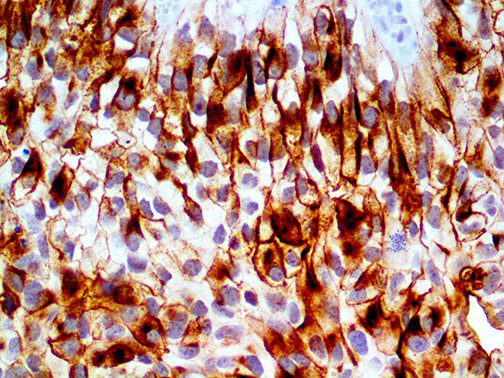

The first cytokines released are interleukin 1β (IL-1β) and tumor necrosis factor-α (TNF-α), which attract a variety of circulating white blood cells (WBCs) to the infection site, including neutrophils, monocytes, macrophages, and natural killer (NK) cells. This response, along with the antipathogenic chemicals released by these cells (i.e., complement), comprise the innate immune response. These cells directly attack the invading pathogen and also release additional cytokines, chief among them interleukin-1 and 6 (IL-6). IL-6 is essential for invoking the adaptive immune response, which calls T-cells, B-cells, and T helper (Th) cells to the infection site. IL-6 also stimulates further recruitment, proliferation and activation of macrophages.

This activation induces inflammatory monocytes to highly express IL-6, starting a localized and then systemic cascade effect that results in hyperproduction of IL-6, which accelerates the inflammatory process. Because IL-6 also increases vascular permeability, excessive levels cause blood vessels to become very leaky. This, along with clotting factors released from vascular endothelial cells, stimulates the coagulation cascade, resulting in microthrombosis (tiny clots), which leads to ischemia and tissue death of the kidney, intestines, heart, liver, brain and extremities.